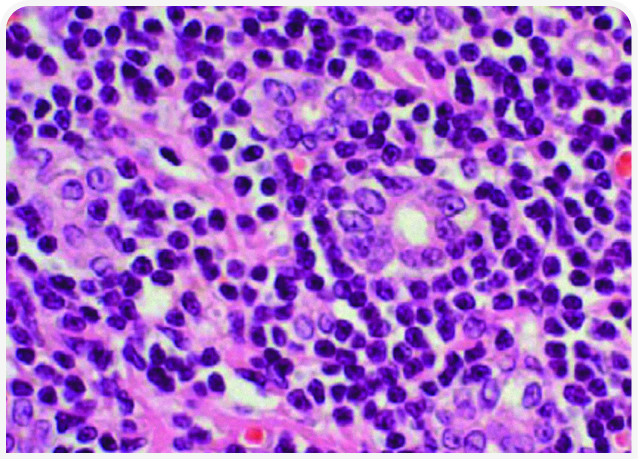

После постановки окончательного (см. гистопатологическую картину на Рисунке 3) или предположительного (как в клиническом случае) диагноза «лимфоцитарный холангит» лечение будет включать неспецифическую поддерживающую терапию и иммунную терапию. К неспецифической терапии относятся инъекции нескольких доз витамина K1 (5 мг на кошку подкожно каждые 24 часа) для нормализации показателей свертывания крови перед проведением тонкоигольной аспирационной биопсии или установкой эзофагального зонда и урсодезоксихолевая кислота (10-15 мг/кг внутрь каждые 24 часа в течение 2-3 месяцев). Этот препарат традиционно используют для стимуляции выведения желчи из билиарной системы; он обладает также рядом дополнительных положительных свойств для пораженной ткани печени (21).

При иммуноопосредованной инфильтрации лимфоцитами назначение антибиотиков не требуется. Даже если изначальной причиной заболевания была бактериальная инфекция, на момент обследования она уже разрешилась. Тем не менее некоторые врачи рекомендуют 2-4-недельный курс антибиотикотерапии в начале лечения для нейтрализации кишечных и/или анаэробных бактерий (см. Клинический случай 2), которые могут являться не причиной, а следствием иммуноопосредованного заболевания (19).

В качестве раннего и эффективного вмешательства у всех кошек, отказывающихся от корма, рекомендуется кормление через эзофагеальный зонд (Рисунок 4). Установка зонда также помогает владельцу ухаживать за кошкой на дому. В Университете Колорадо используют троакар и эзофагеальный зонд калибра 14Fr или производства MILA International, Inc.1

Специфическое лечение лимфоцитарного холангита заключается в назначении глюкокортикоидов, препаратом выбора считают преднизолон. Некоторые врачи начинают с дозы 4 мг/кг/день, большинство – с дозы ближе к 2 мг/кг/день, но во всех случаях дозу медленно снижают в течение 3 месяцев.

Ответ на терапию можно оценивать по ряду показателей, например по клиническим проявлениям, цвету слизистой, изменениям уровня печеночных ферментов и общего билирубина.